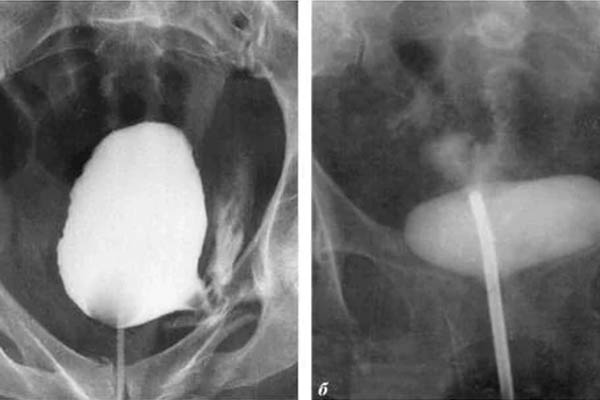

Saya ingin menunjukkan beberapa foto tentang apa yang terjadi pada sistem genitourinari dan organ dalam lainnya dari seorang pria ketika dia berhenti berhubungan seks.

Seperti inilah peradangan prostat karena stagnasi di dalamnya (dengan tidak adanya pengosongan testis, yang terjadi saat berhubungan seks). Peradangan yang berkepanjangan pertama-tama mengarah ke adenoma, dan kemudian ke kanker prostat (dari mana, menurut statistik, 38% pria meninggal). Dengan tidak adanya seks, ini selalu terjadi, itulah sebabnya adenoma dianggap sebagai penyakit orang tua.